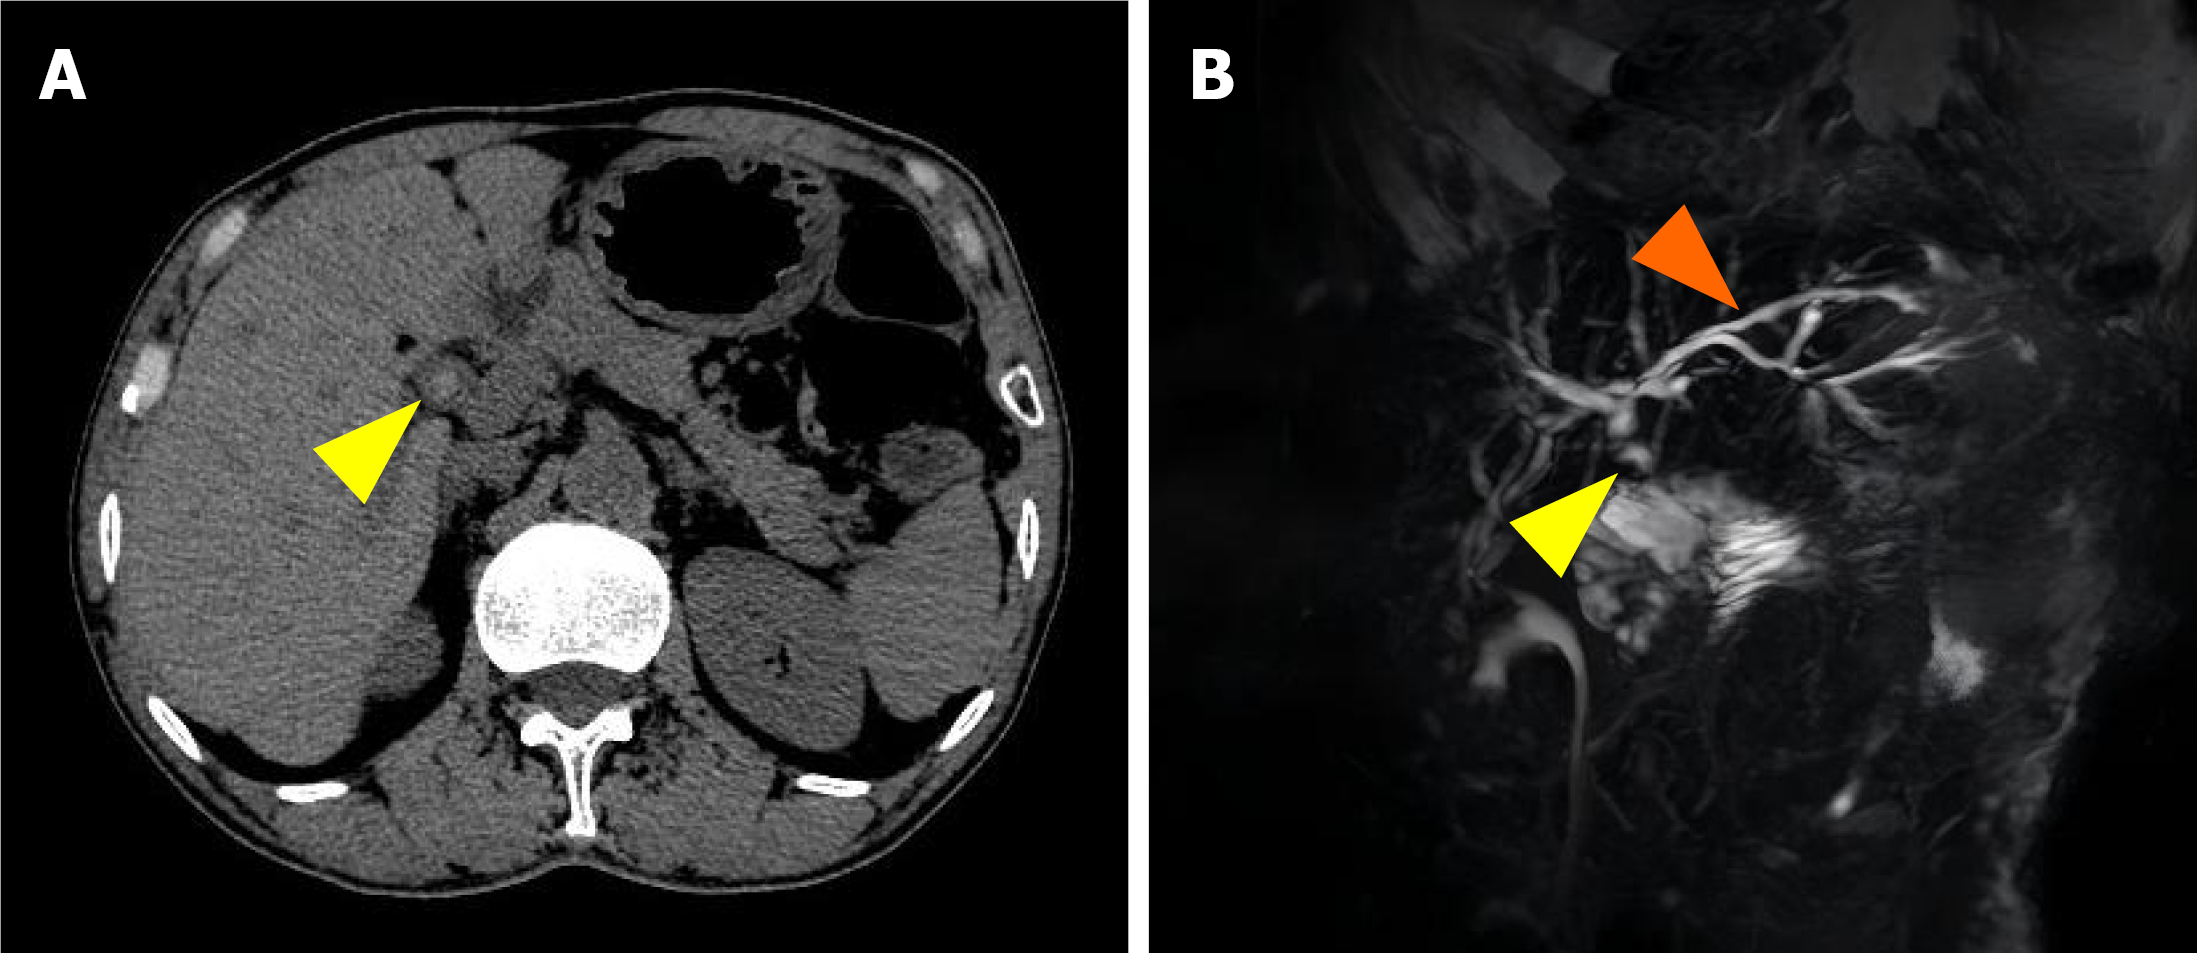

Figure 1 Imaging confirmation of common hepatic duct stones following pancreaticoduodenectomy.

A: Contrast-enhanced computed tomo graphy image revealing a hyperdense focus within the common hepatic duct (yellow arrowheads); B: Magnetic resonance cholangiopancreatography demonstrating a filling defect in the common hepatic duct (yellow arrowheads) with mild intrahepatic ductal dilatation (orange arrowheads).